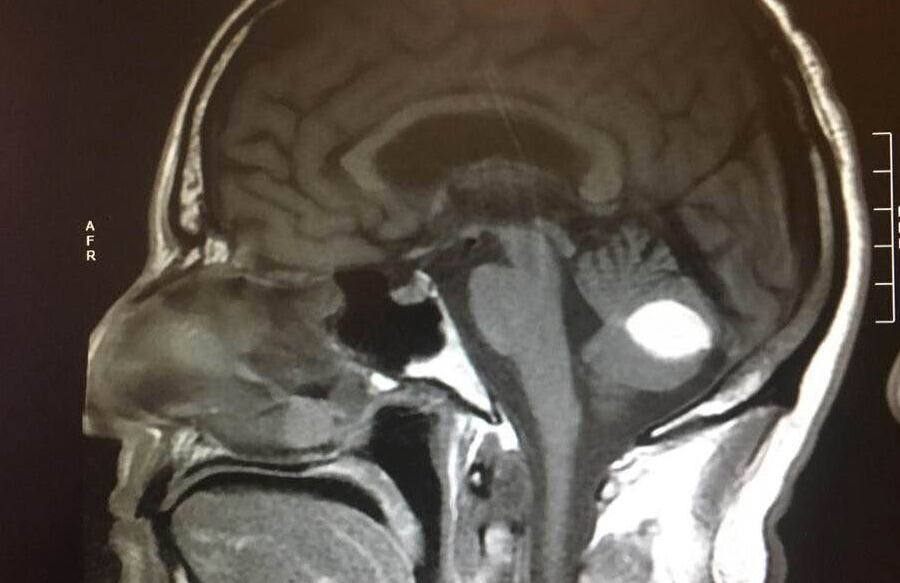

«Si no crees en Dios y crees que no hace milagros, explica esto. El tumor desapareció y los médicos no puede explicarlo, están de acuerdo en que se trata de un milagro», escribió en Facebook mostrando una fotografía de la tomografía en la cabeza que le hicieron en el hospital.

«Esto (la tomografía) fue en julio del 2018, en la parte inferior derecha se puede ver el tumor en el lugar del círculo blanco, ahora ha desaparecido», explicó el paciente.